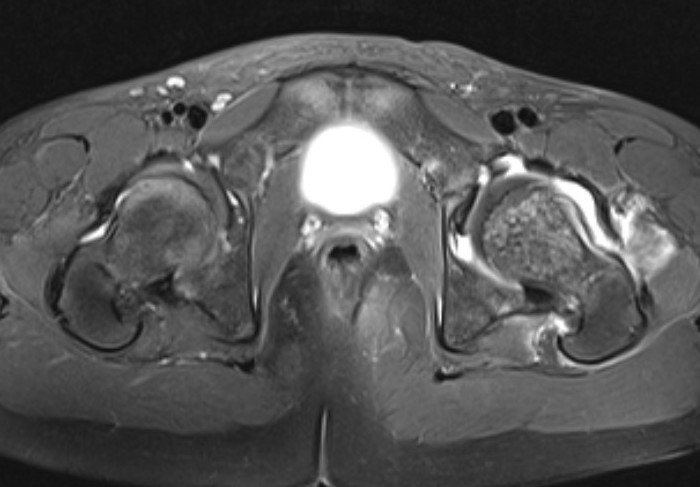

MRI

Adam et al Eur J Radiol Open 2022

- meta-analysis of MRI distinguishing between transient and septic arthitis

- bone marrow changes - 99% specific for septic arthritis

Septic arthritisSeptic arthritis

Fluid in hip joint

Hip OMHip OM

Subluxation of the hip joint with effusion and bone marrow changes

Proximal femoral osteomyelitis

Bone marrow edema and osteomyelitis in the femoral head